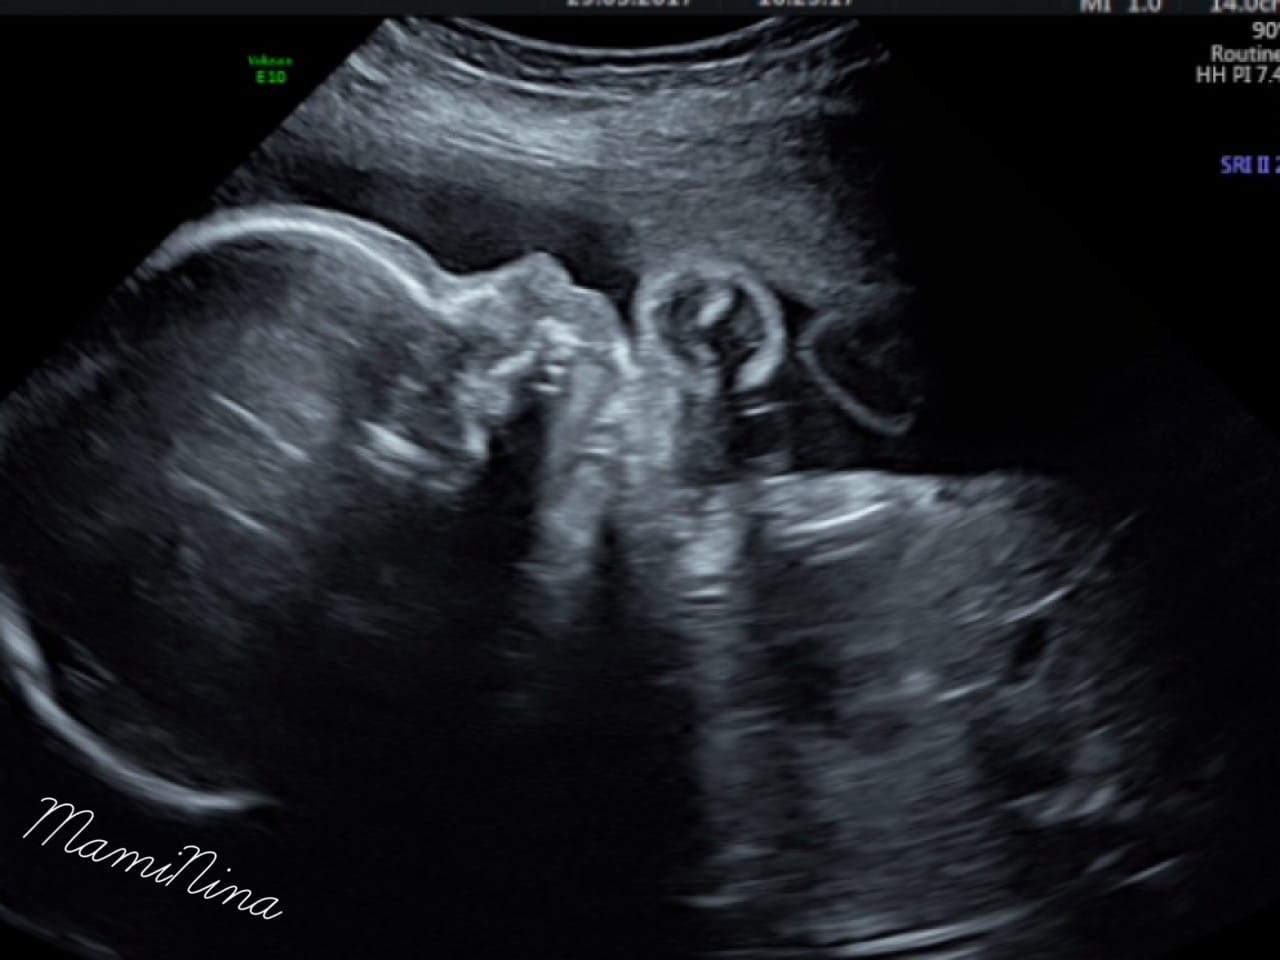

In resnično nam ni prav nič žal. Videli smo vse in to zelo dobro. Obrazek je seveda gospodična precej pokrivala, tako kot ga je tudi njena sestrica. In ne le to, prav tako kot sestrica, je tudi tale gospodična obrnjena v desno, pred obrazkom se nahaja tudi ena nogica in seveda kraljuje na svoji mali ritki.

Pogledali smo v njeno glavico, preverili srček, nogice, rokice, obrazek, mehur in na sploh vse. In vse izgleda prav super.

Srček utripa z 132 udarci, mala pa ima že približno nekje 830 g (če bo teža naraščala tako kot do sedaj, predvidevam, da bo precej lahka, seveda pa so tudi njene mere manjše).